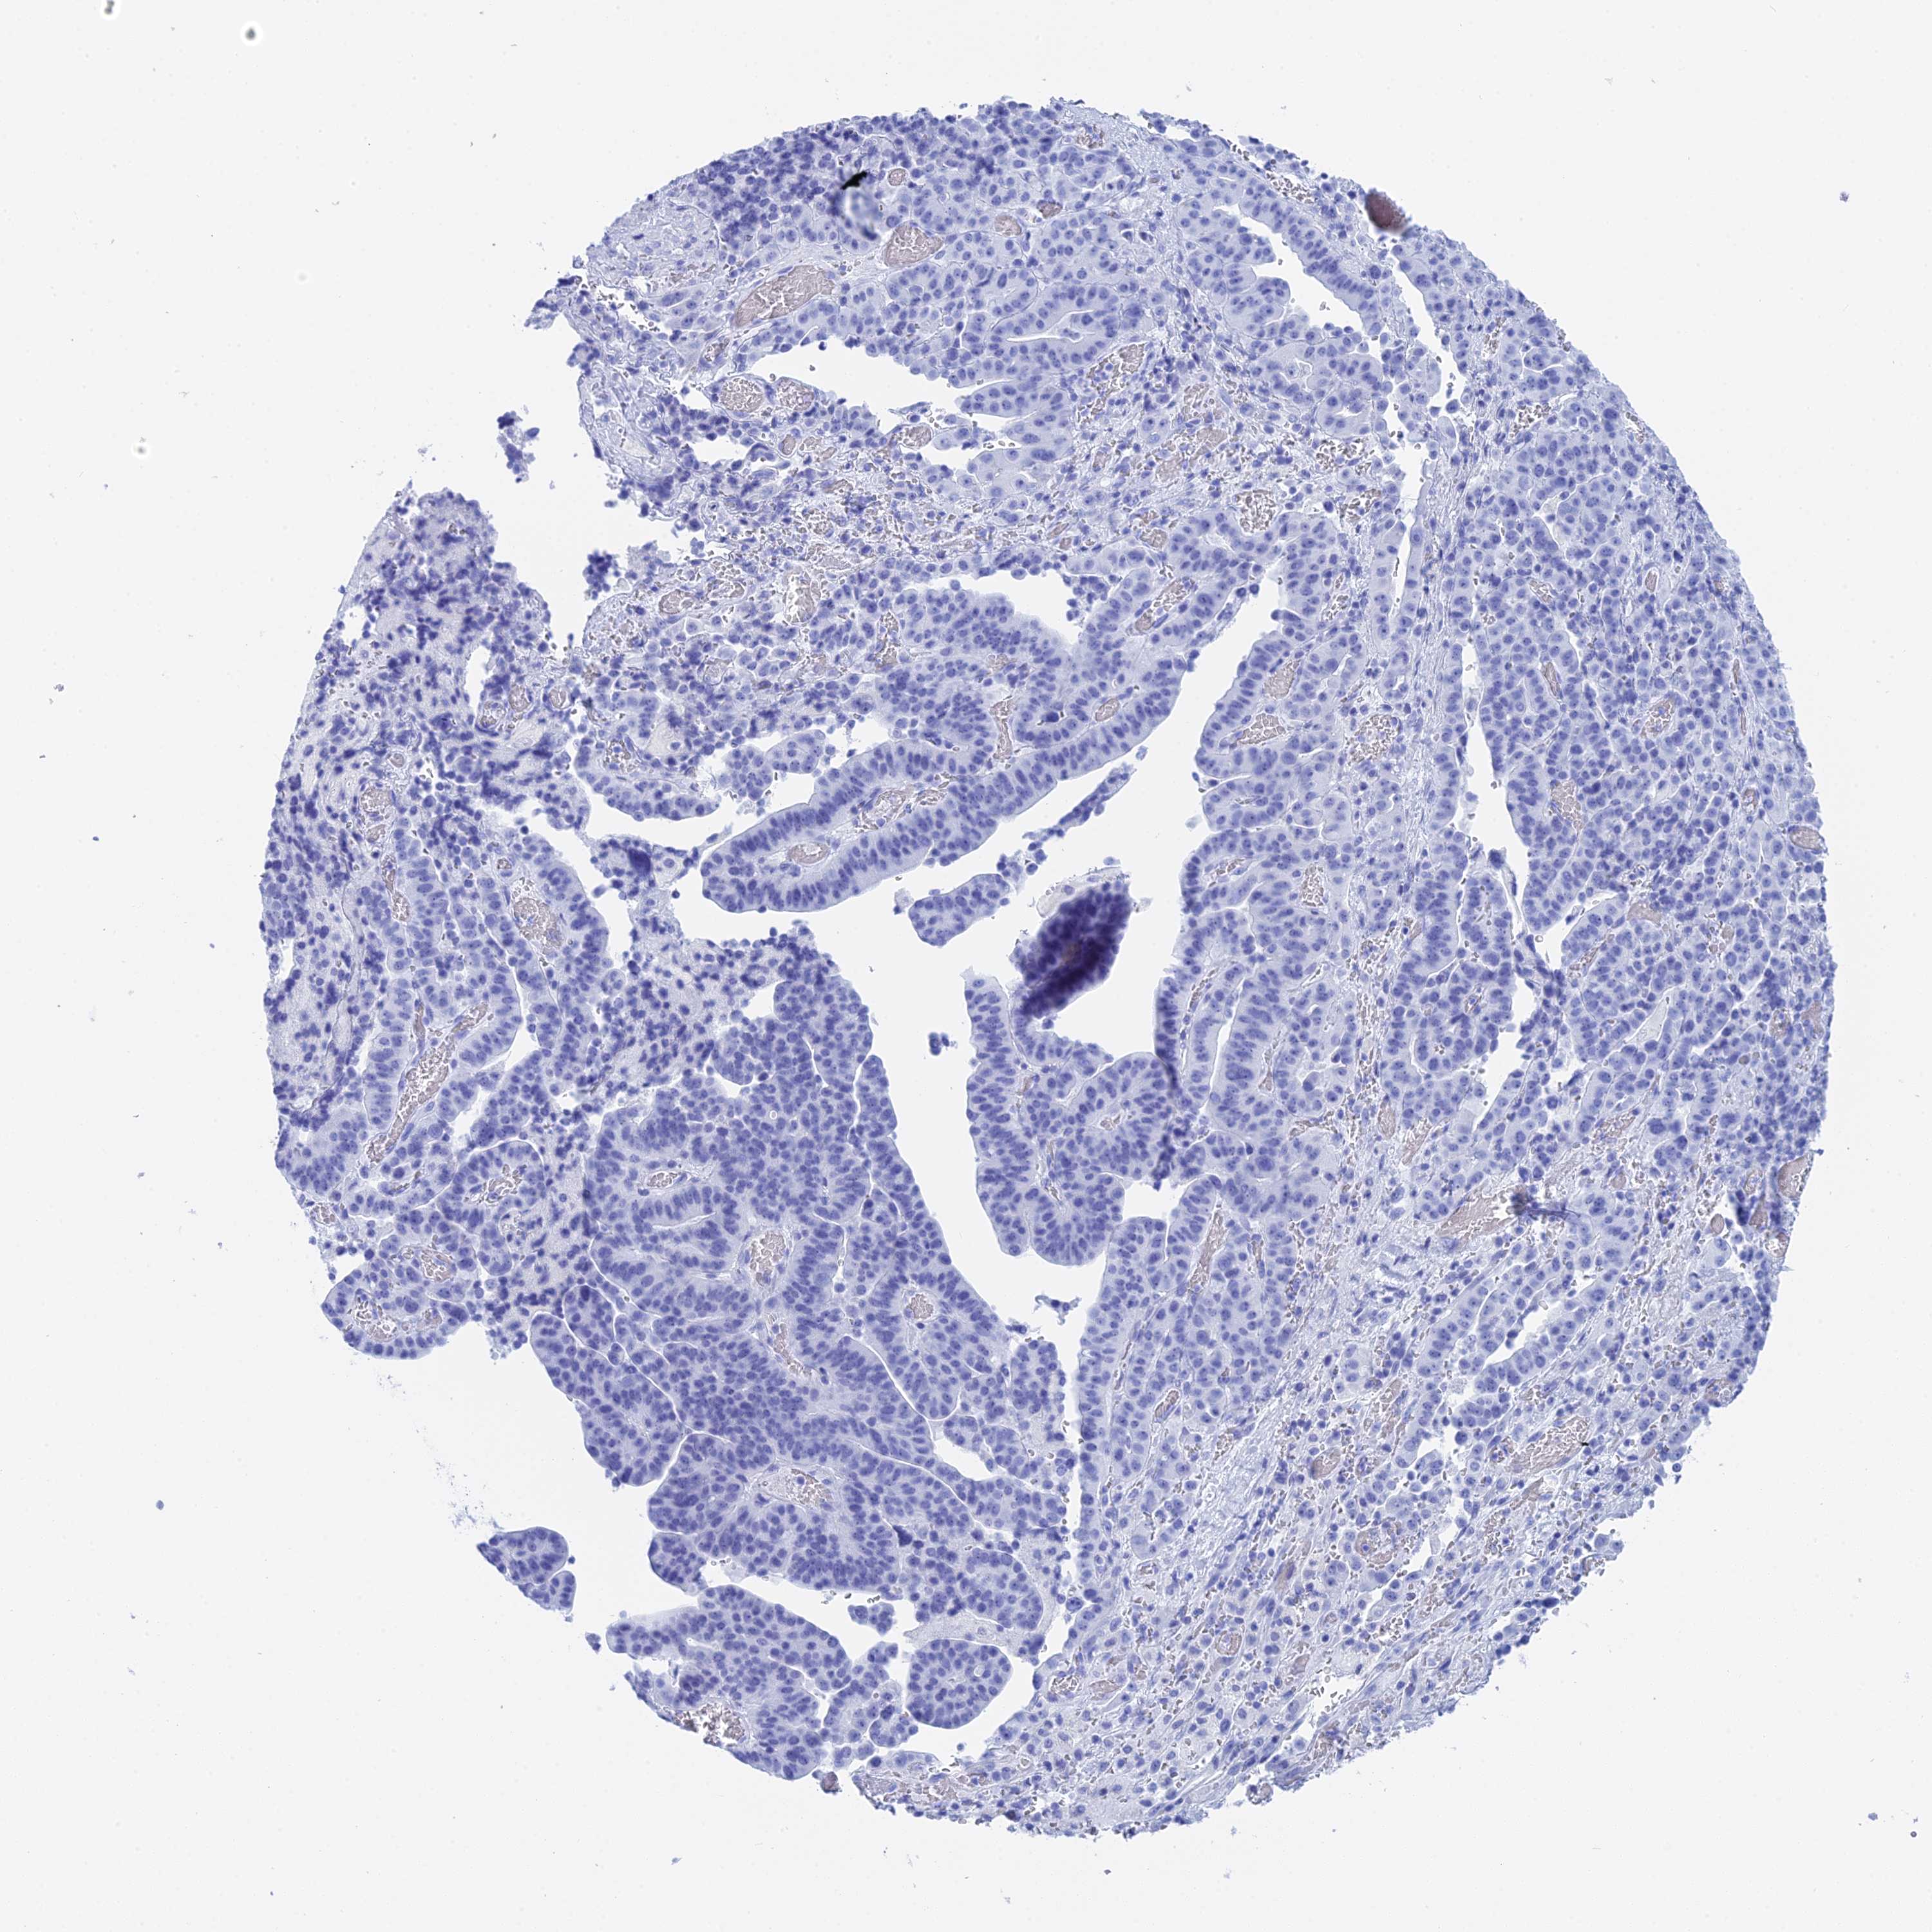

STOMACH CANCER - Protein expressioni

A mouse-over function shows sample information and annotation data. Click on an image to view it in a full screen mode. Samples can be filtered based on level of antibody staining by selecting one or several of the following categories: high, medium, low and not detected. The assay and annotation is described here.

Note that samples used for immunohistochemistry by the Human Protein Atlas do not correspond to samples in the TCGA dataset.

Antibody stainingi

Antibody staining in the annotated cell types in the current human tissue is reported as not detected, low, medium, or high, based on conventional immunohistochemistry profiling in selected tissues. This score is based on the combination of the staining intensity and fraction of stained cells.

Each image is clickable and will lead to virtual microscopy that enables deeper exploration of all samples and also displays staining intensity scores, fraction scores and subcellular localization as well as patient and tissue information for each sample.

Antibody HPA041915

Antibody HPA042513

Staining

High

Medium

Low

Not detected

Intensity

Strong

Moderate

Weak

Negative

Quantity

>75%

75%-25%

<25%

None

Location

Nuclear

Cytoplasmic/membranous

Cytoplasmic/membranous,nuclear

Adenocarcinoma, NOS